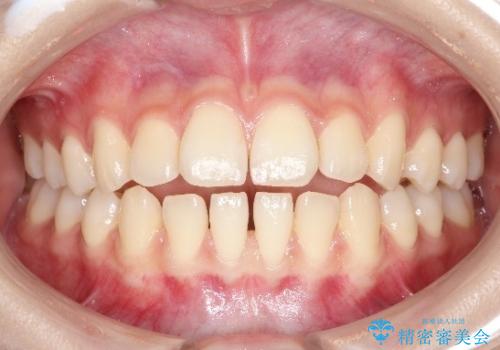

前歯の部分矯正 インビザラインエクスプレスパッケージ

部分矯正は治療が短期間で終わる、費用が安いというメリットがありますが、時に治療において理想的な結果を目指せないことがあります。

今回は再矯正ということもあり非常に満足いただくことができました。